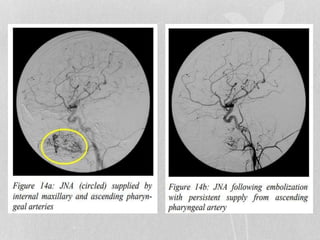

•Angiography:

b/l vascular supply is around 36% hence both carotid systems

require angiographic evaluation

1. Assess vascular supply of JA

2. Allow embolization of feeding vessels prior to surgery

More as a surgical treatment adjuvant via possibility of

embolization rather than diagnostic tool

MR angiography is least invasive form of vascular imaging

that will show size feeding vessels

Vascular blush seen in postnasal space and adjacent areas is

diagnostic